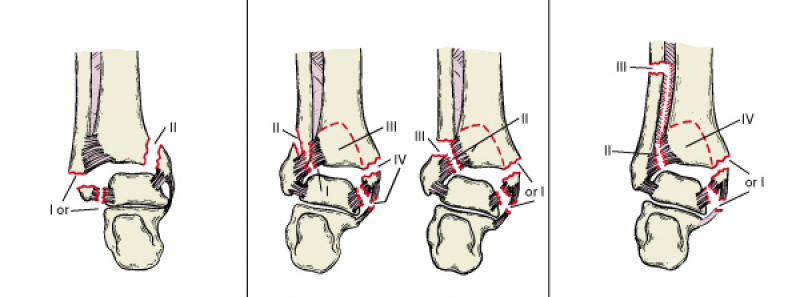

Lauge-Hansen分型是以踝关节骨折的受伤机制和病理生理为基础(图3)。

Lauge-Hansen根据尸体解剖和临床实践研究,把踝关节损伤时外力作用的方向,足所处的位置结合起来提出了Lauge-Hansen分型法。每型的前半指受伤时足所处的位置—旋前或旋后,后半部分则指外力的方向—外旋、外展或内收。

图3 踝关节骨折的Lauge-Hansen分型